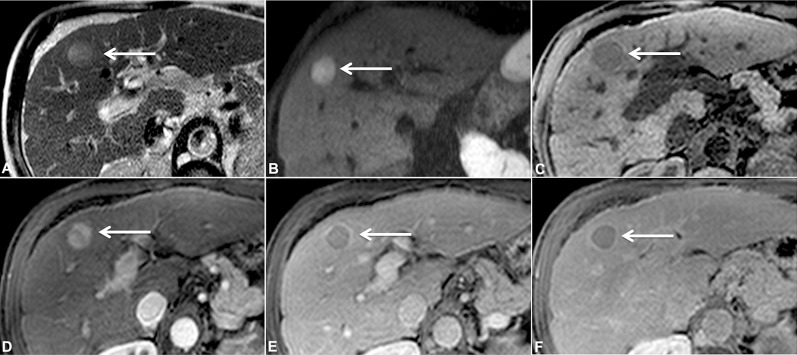

Fig. 2. Multiphase, contrast-enhanced MRI in a 64 year-old man with cirrhosis.

The lesion (white arrows) shows characteristic findings of HCC, including increased T2 signal (A), restricted diffusion (B; obtained at a b-value of 700 s/mm2), decreased signal on T1 precontrast image (C), arterial hyperenhancement (D), washout with pseudocapsule on venous phase (E), and washout with pseudocapsule on delayed 3-m phase (F).